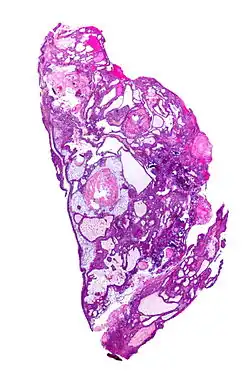

Obraz histologiczny

Guz może mikroskopowo przypominać szkliwiaka (adamantinoma) i tworzyć wyspy oraz sznury komórek nabłonka wielowarstwowego płaskiego lub nabłonka walcowatego w łącznotkankowym podścielisku (wariant szkliwiakowaty, adamantinomatous variant). W obrazie histologicznym można też stwierdzić rogowacenie, zwapnienia, torbiele, włóknienie i przewlekły stan zapalny. Druga odmiana czaszkogardlaka, odmiana brodawkowata (papillary variant), tworzy gniazda komórek nabłonka płaskiego, bez rogowacenia, zwapnień ani torbieli[3].